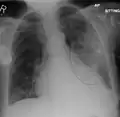

Normal AP CXR

AP CXR showing left lower lobe pneumonia associated with a small left sided pleural effusion -

The discovery of x-rays made it possible to determine the anatomic type of pneumonia without direct examination of the lungs at autopsy and led to the development of a radiological classification. Early investigators distinguished between typical lobar pneumonia and atypical (e.g. Chlamydophila) or viral pneumonia using the location, distribution, and appearance of the opacities they saw on chest x-rays. Certain x-ray findings can be used to help predict the course of illness, although it is not possible to clearly determine the microbiologic cause of a pneumonia with x-rays alone.